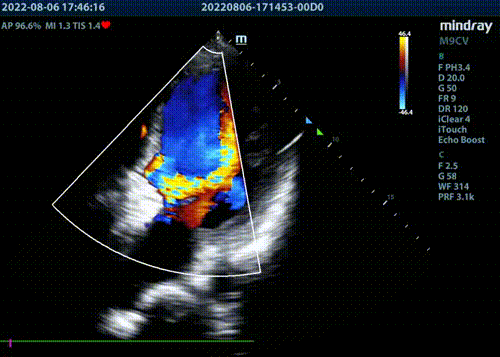

超声提示2枚封堵器位置良好,瓣周反流明显减少,但仍有少-中量瓣周反流。遂在已植入封堵器旁再次探查,并通过瓣周漏。因交换鞘管困难,遂采用LOOP法建立轨道,引导输送鞘管通过瓣周漏。

释放第三枚封堵器,选用6mmADOII,释放后造影显示无明显瓣周反流。

术后超声提示微量瓣周反流。